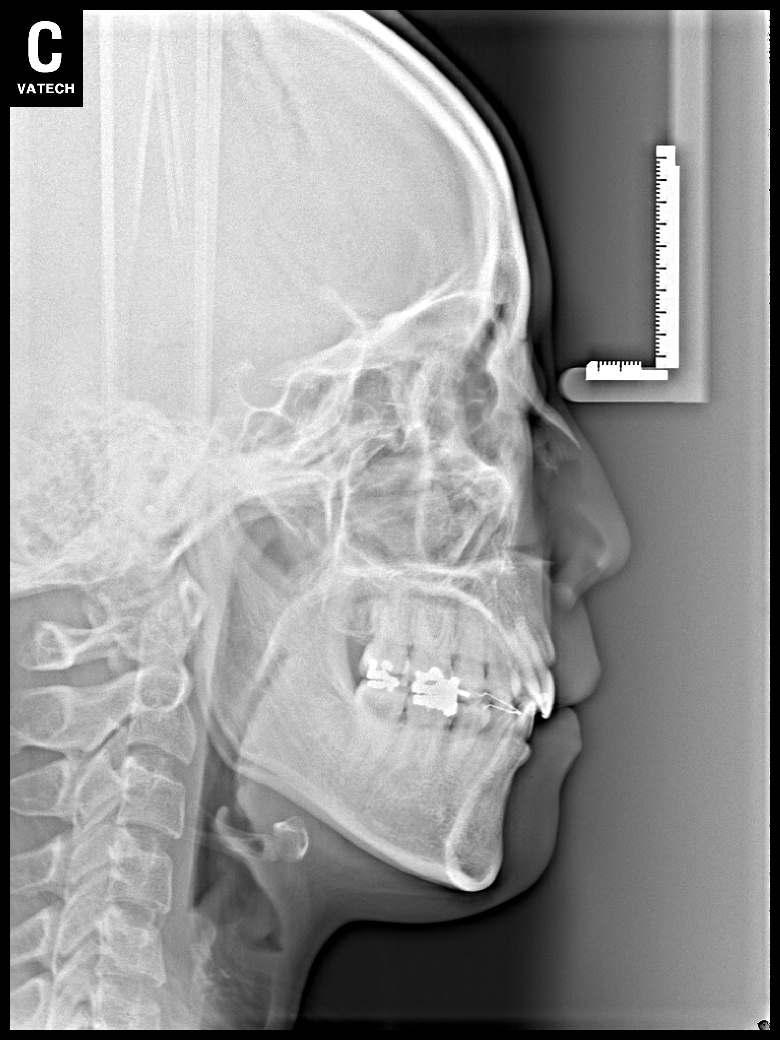

치료 후 사진입니다.